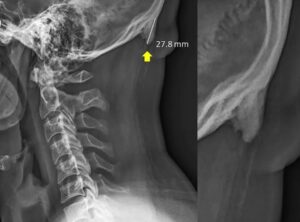

En la parte posterior del cráneo se ubica una protuberancia occipital externa, una estructura palpable que puede verse afectada por ciertos movimientos. “Una investigación publicada recientemente, indica que esta protuberancia y ligamento ha sufrido un grado de tensión, porque el mismo ligamento ha traccionado el hueso occipital, provocando un crecimiento de esta protuberancia. Es algo muy común en escaladores, basquetbolistas y jugadores de beisbol. Por otro lado, los autores del estudio indican que una de las causas -de este crecimiento- podría ser la postura adquirida para trabajar con teléfonos móviles o el computador”, sostuvo.